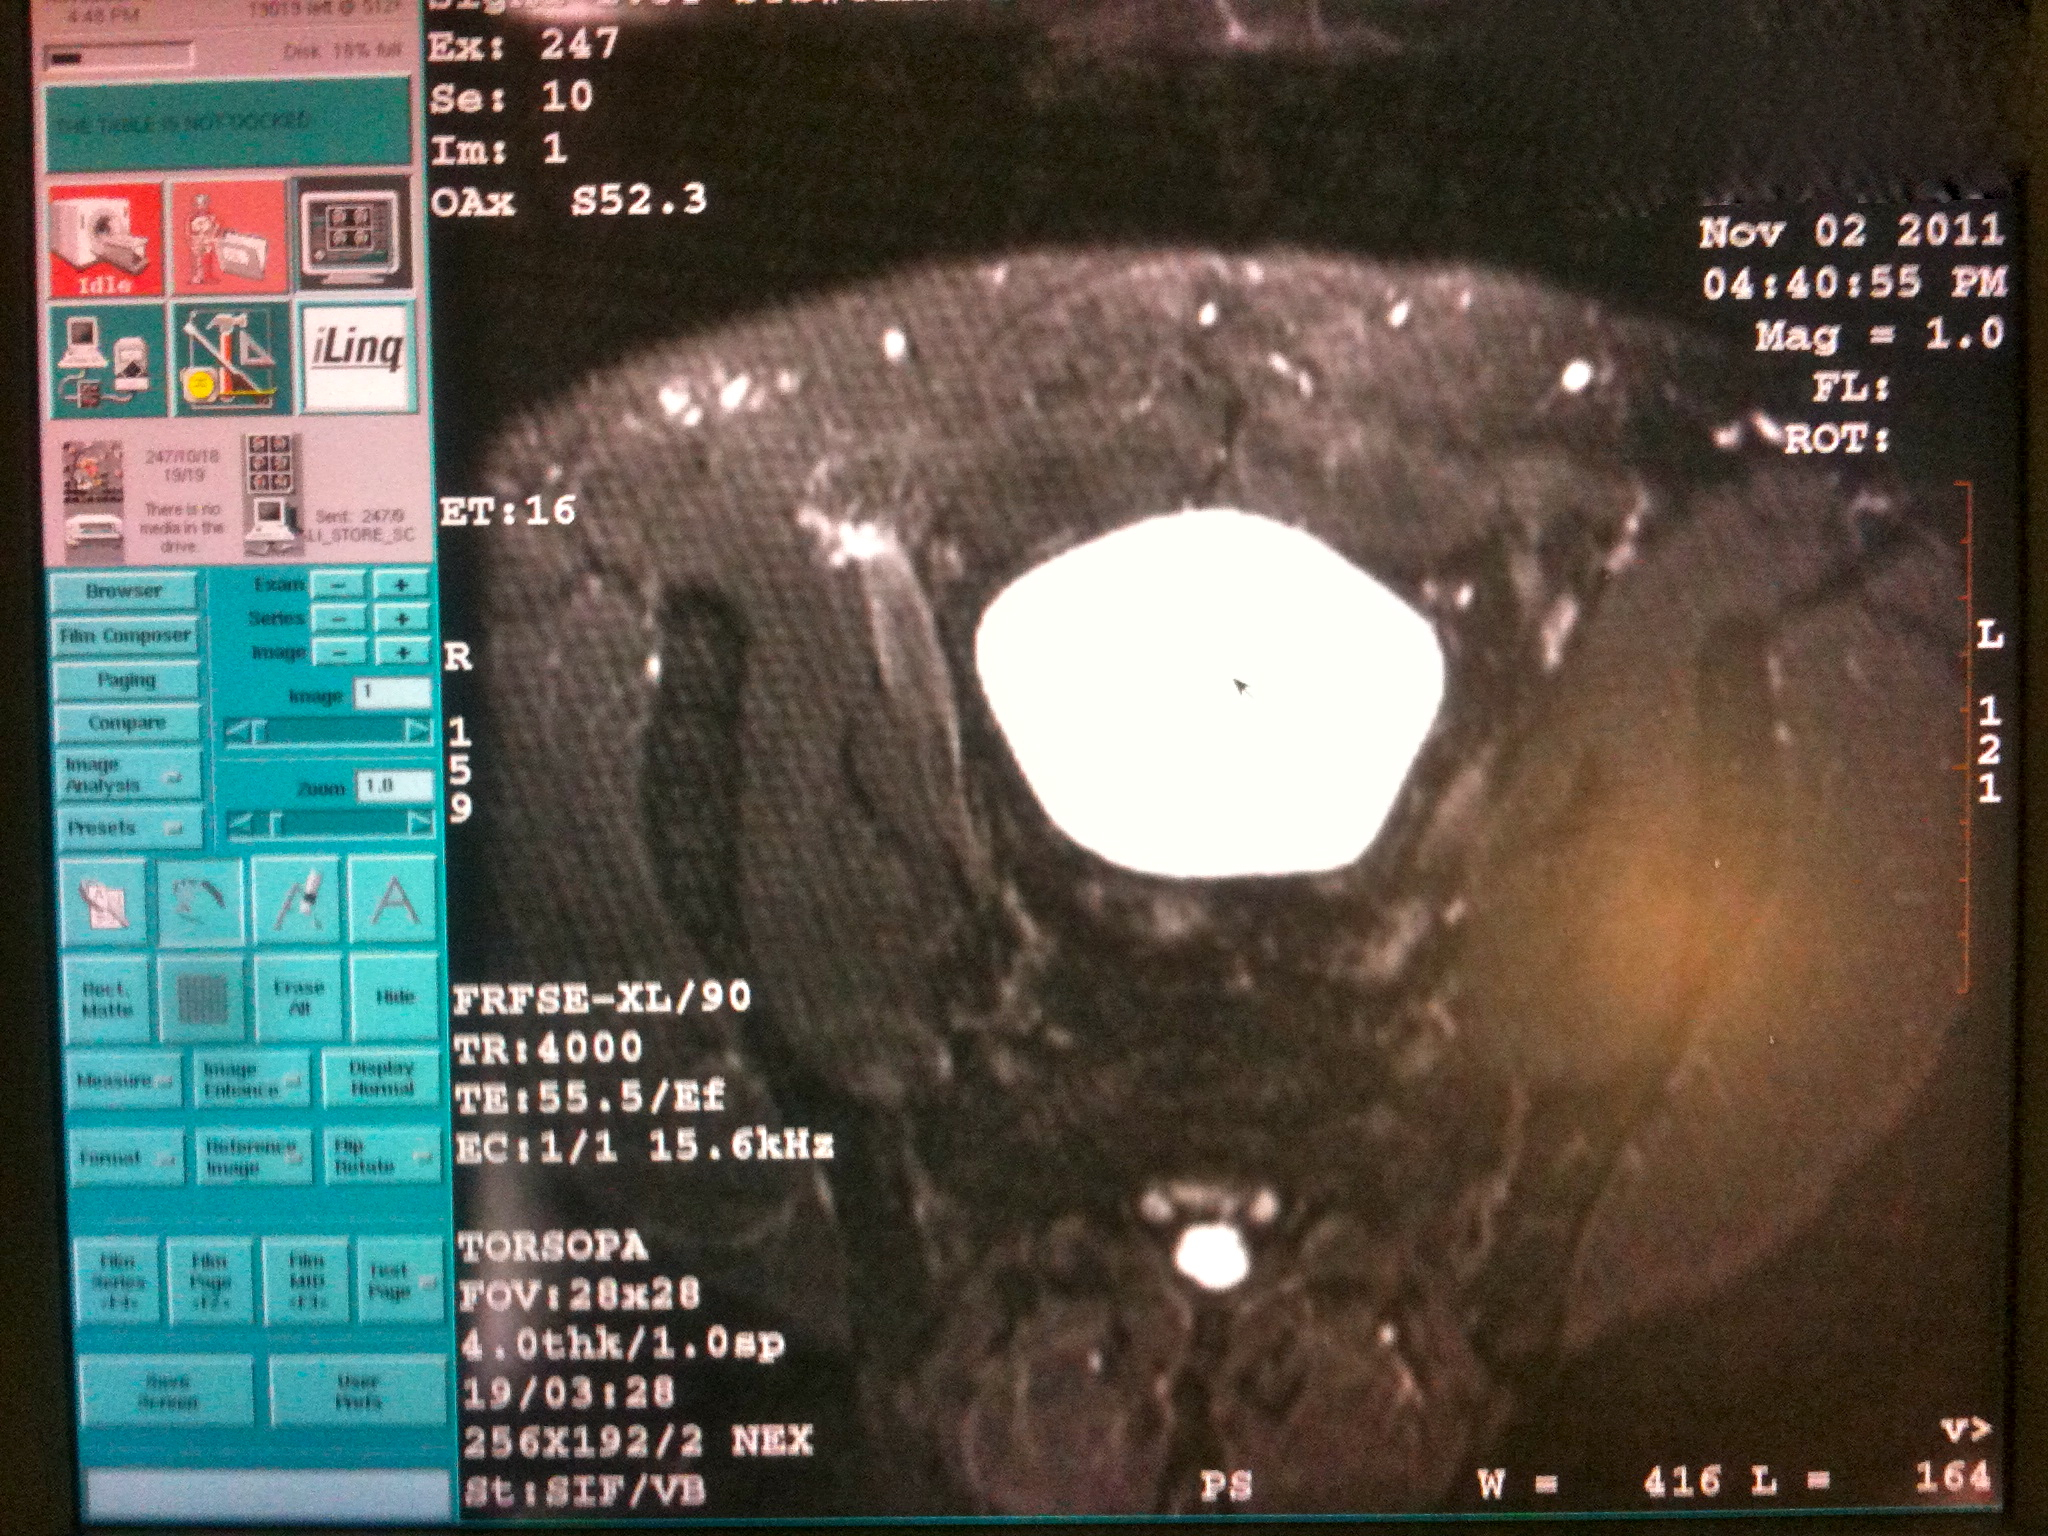

Dr. WW called back again to let me know he’d reviewed my MRI with Dr. Stilp – an Orthopedic Surgeon across the street at the Boulder Surgery Center. She concurs with the radiology diagnosis of arthritis in my symphysis pubis and wants me to call her to schedule myself to receive a fluoroscopic-guided shot of cortisone. Dr. WW actually let me agree first that I was interested in receiving the shot. He might have been following some ethics protocol. He seemed happy with my decision though. And he related to me that I’m only the second case of symphysis pubis arthritis he’s treated. The other guy was a few years ago. That guy was in his 30s which makes me feel better about this not simply being about my age. Dr. WW ended the call by giving me the phone number to Dr. Stilp’s nurse Heather, to setup the procedure.